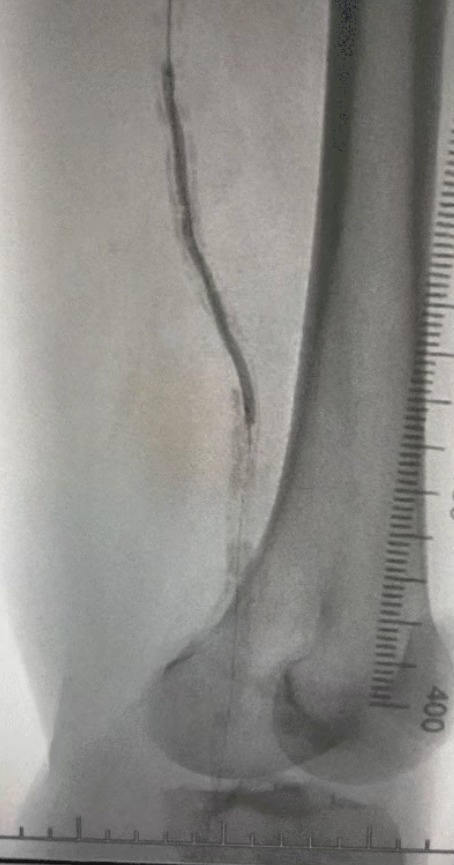

· Imagem pré-operatória: estenose calcificada difusa grave em artérias bilaterais dos membros inferiores

Dada a condição vascular complexa, selecionamos o ThorCrack Peripheral IVL Balloon Dilatation Catheter System. Devido à limitada tolerância do paciente, foram realizados procedimentos intervencionistas estadiados em ambos os membros inferiores.

Resultado cirúrgico

Pós-procedimento, a estenose arterial melhorou significativamente, o fluxo sanguíneo aumentou e a temperatura da pele aumentou. Nenhuma complicação pós-operatória ocorreu. Tanto o paciente quanto a equipe cirúrgica ficaram muito satisfeitos com os resultados.